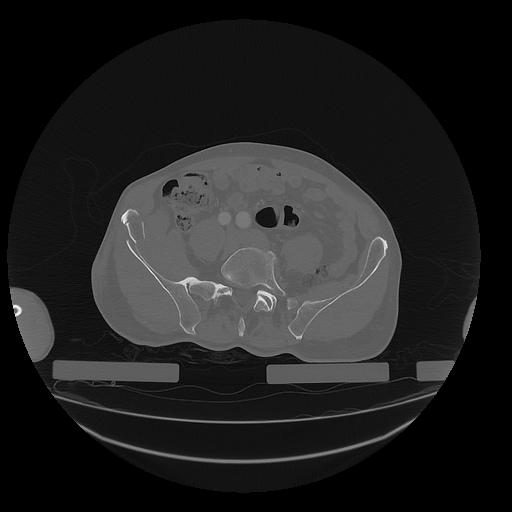

31 PULMON,CE,Vol,1.0,PULMON,,